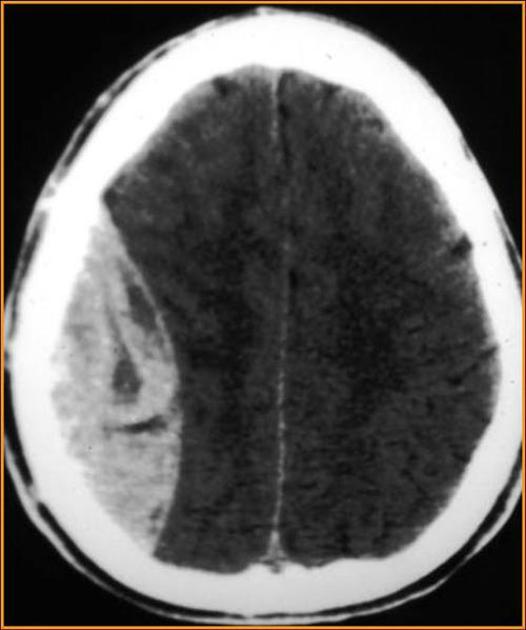

What type of bleed is this?

can it cross suture lines?

epidural hematomas CANNOT cross suture lines

Which injuries are associated with a basilar skull fracture?

Epidural hematoma → injury middle meningeal artery